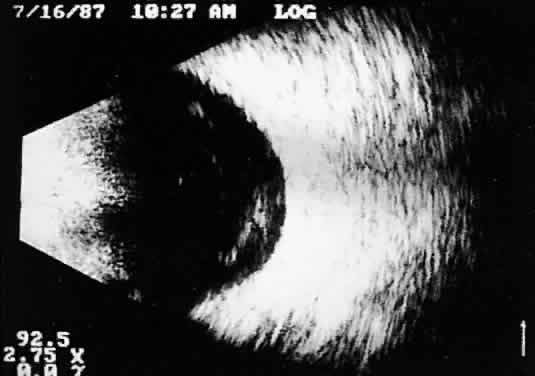

Fig. 9. Contact B-scan: total retinal detachment, anteroposterior view. Characteristic V-shaped appearance with attachment to the optic nerve head.